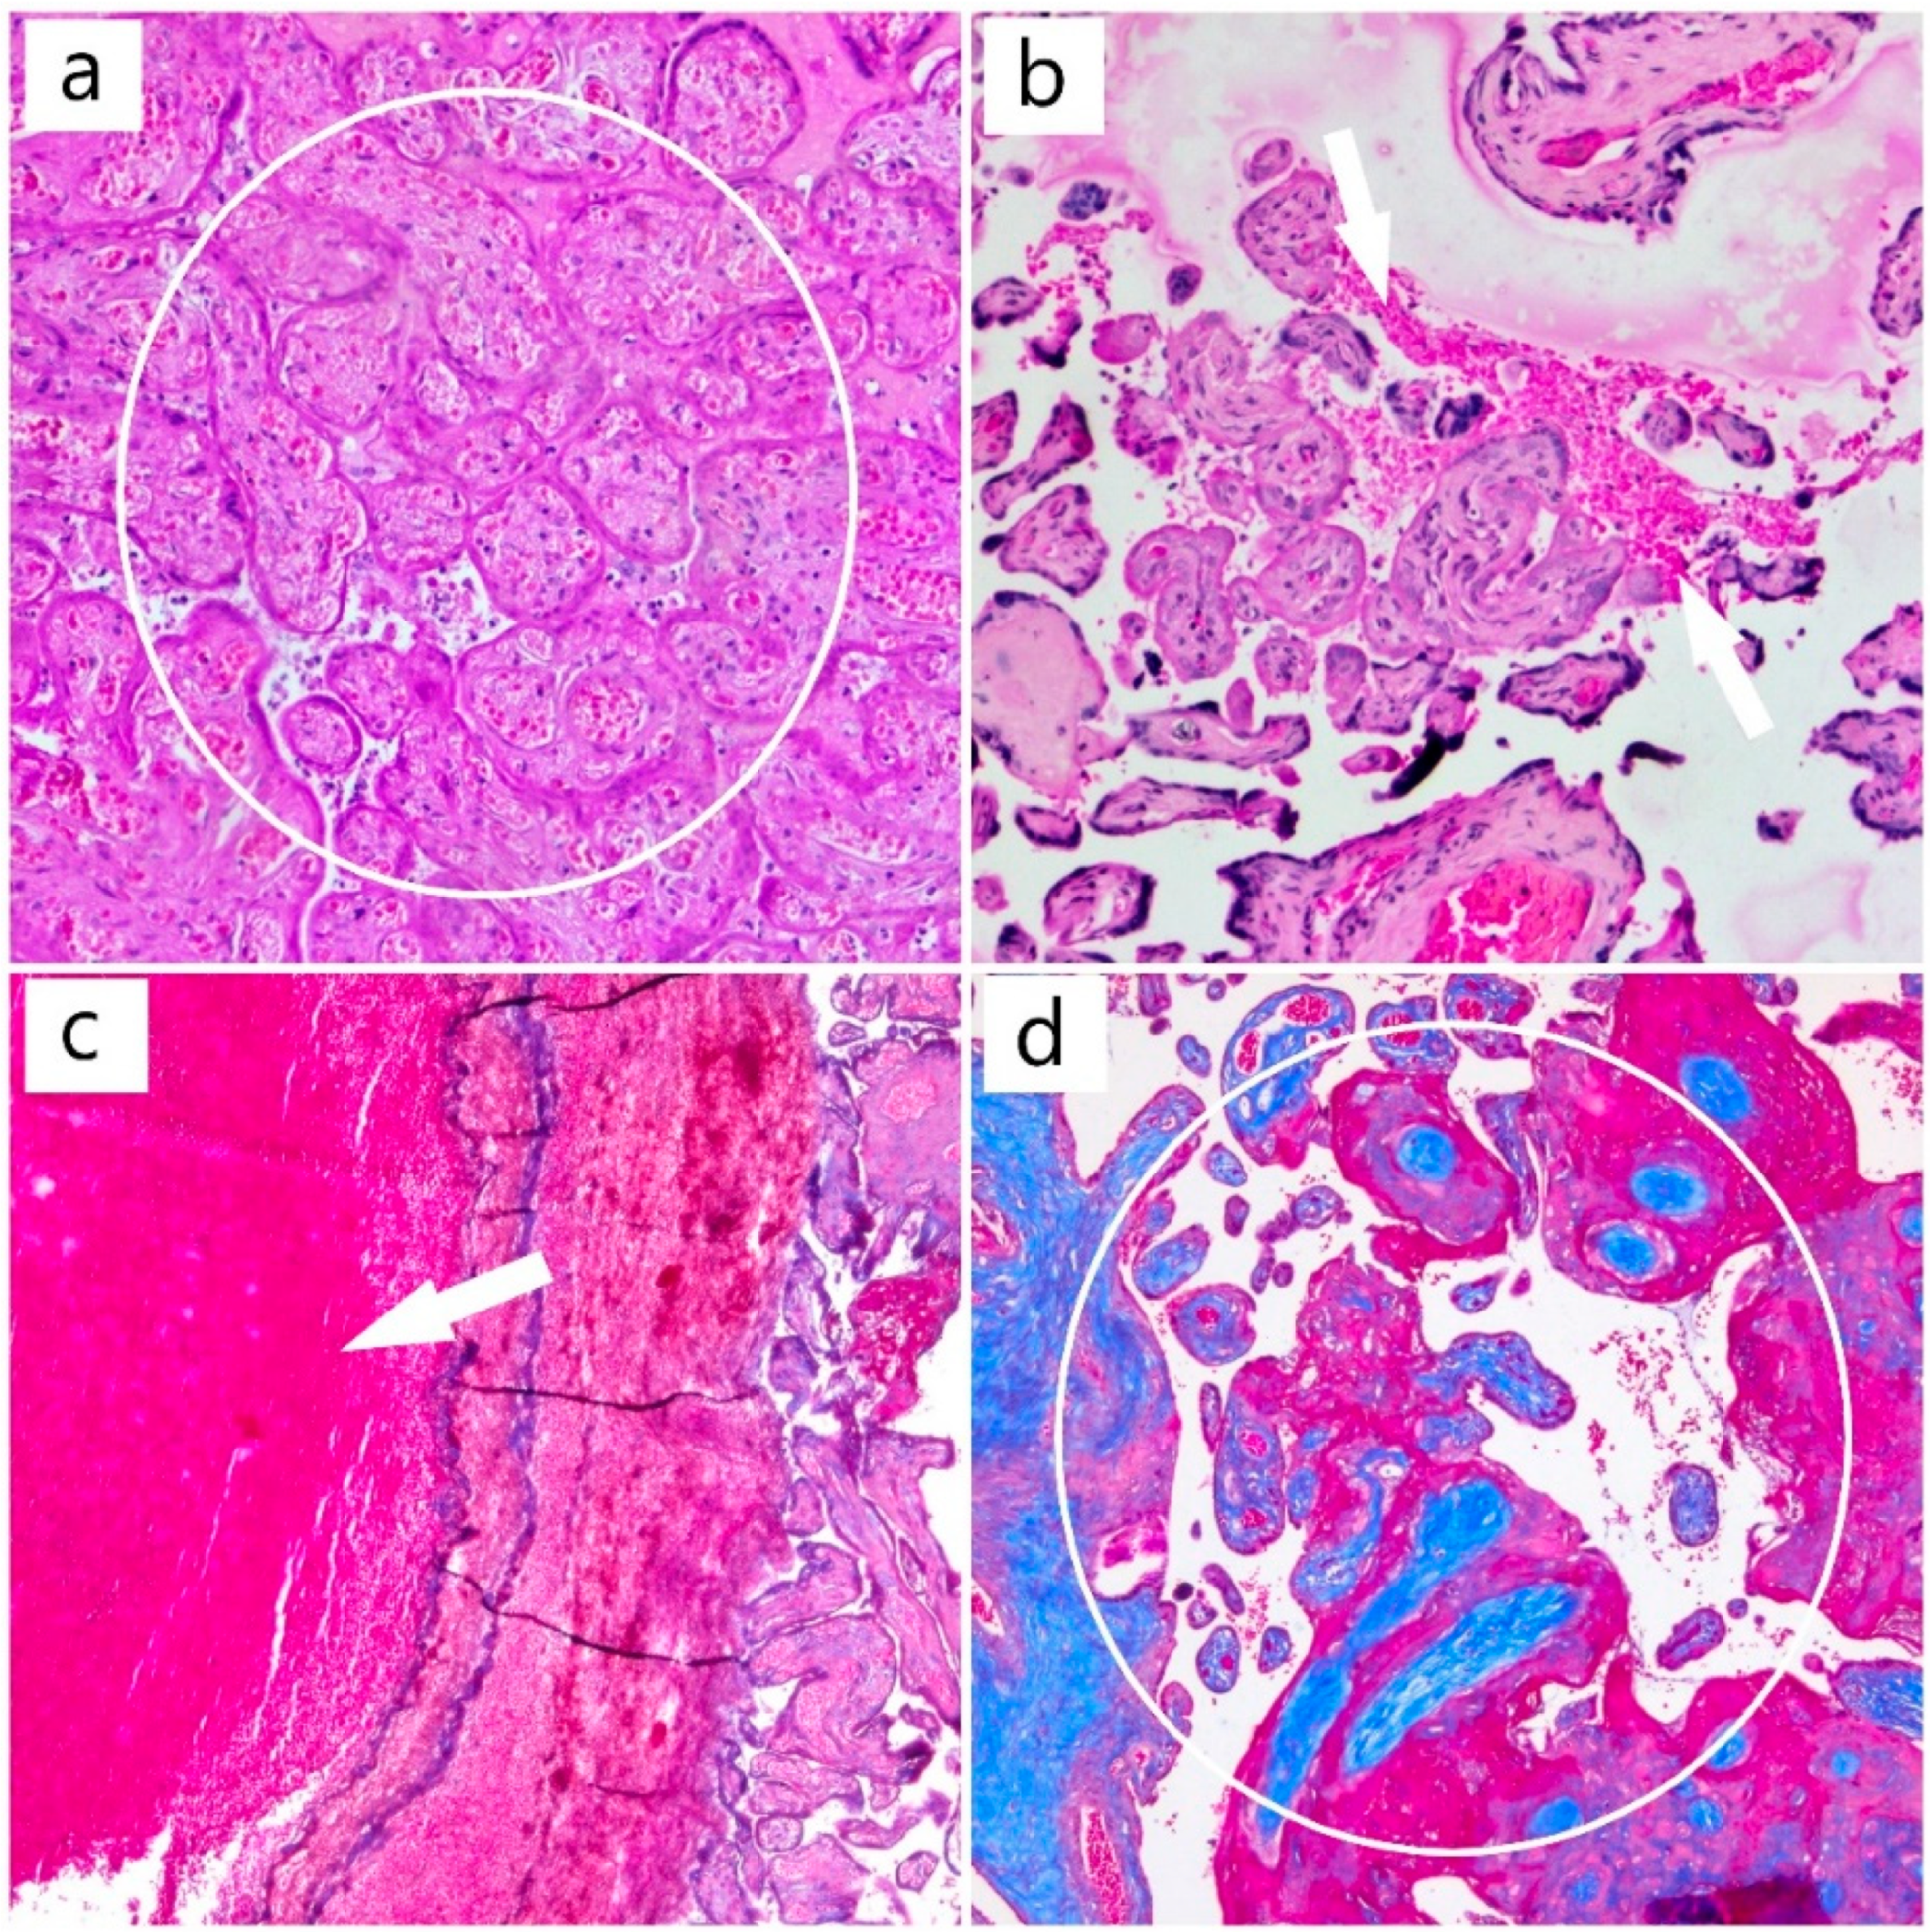

2. Case Report